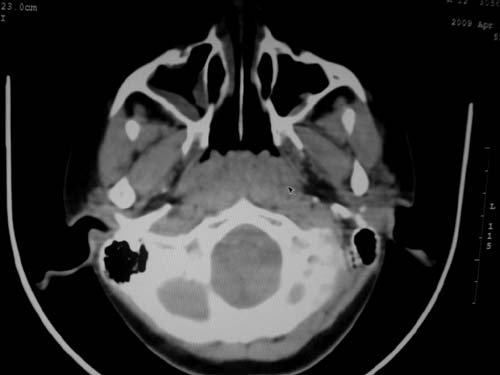

标题: CT19740:女,12岁,鼻塞,流黄鼻涕。 [打印本页]

标题: CT19740:女,12岁,鼻塞,流黄鼻涕。

双侧上颌窦炎,增殖腺肥大。

1)双侧上颌窦炎。2)鼻咽腺样体肥大。